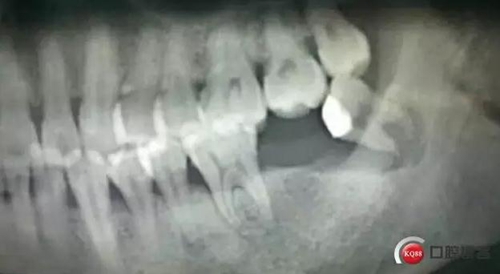

輔助檢查:曲面體層片示:38根尖區(qū)見(jiàn)一類(lèi)圓形透射影,周緣可見(jiàn)明顯白色骨質(zhì)線(xiàn)。

確定診斷:38近中阻生 根尖囊腫 繼發(fā)感染